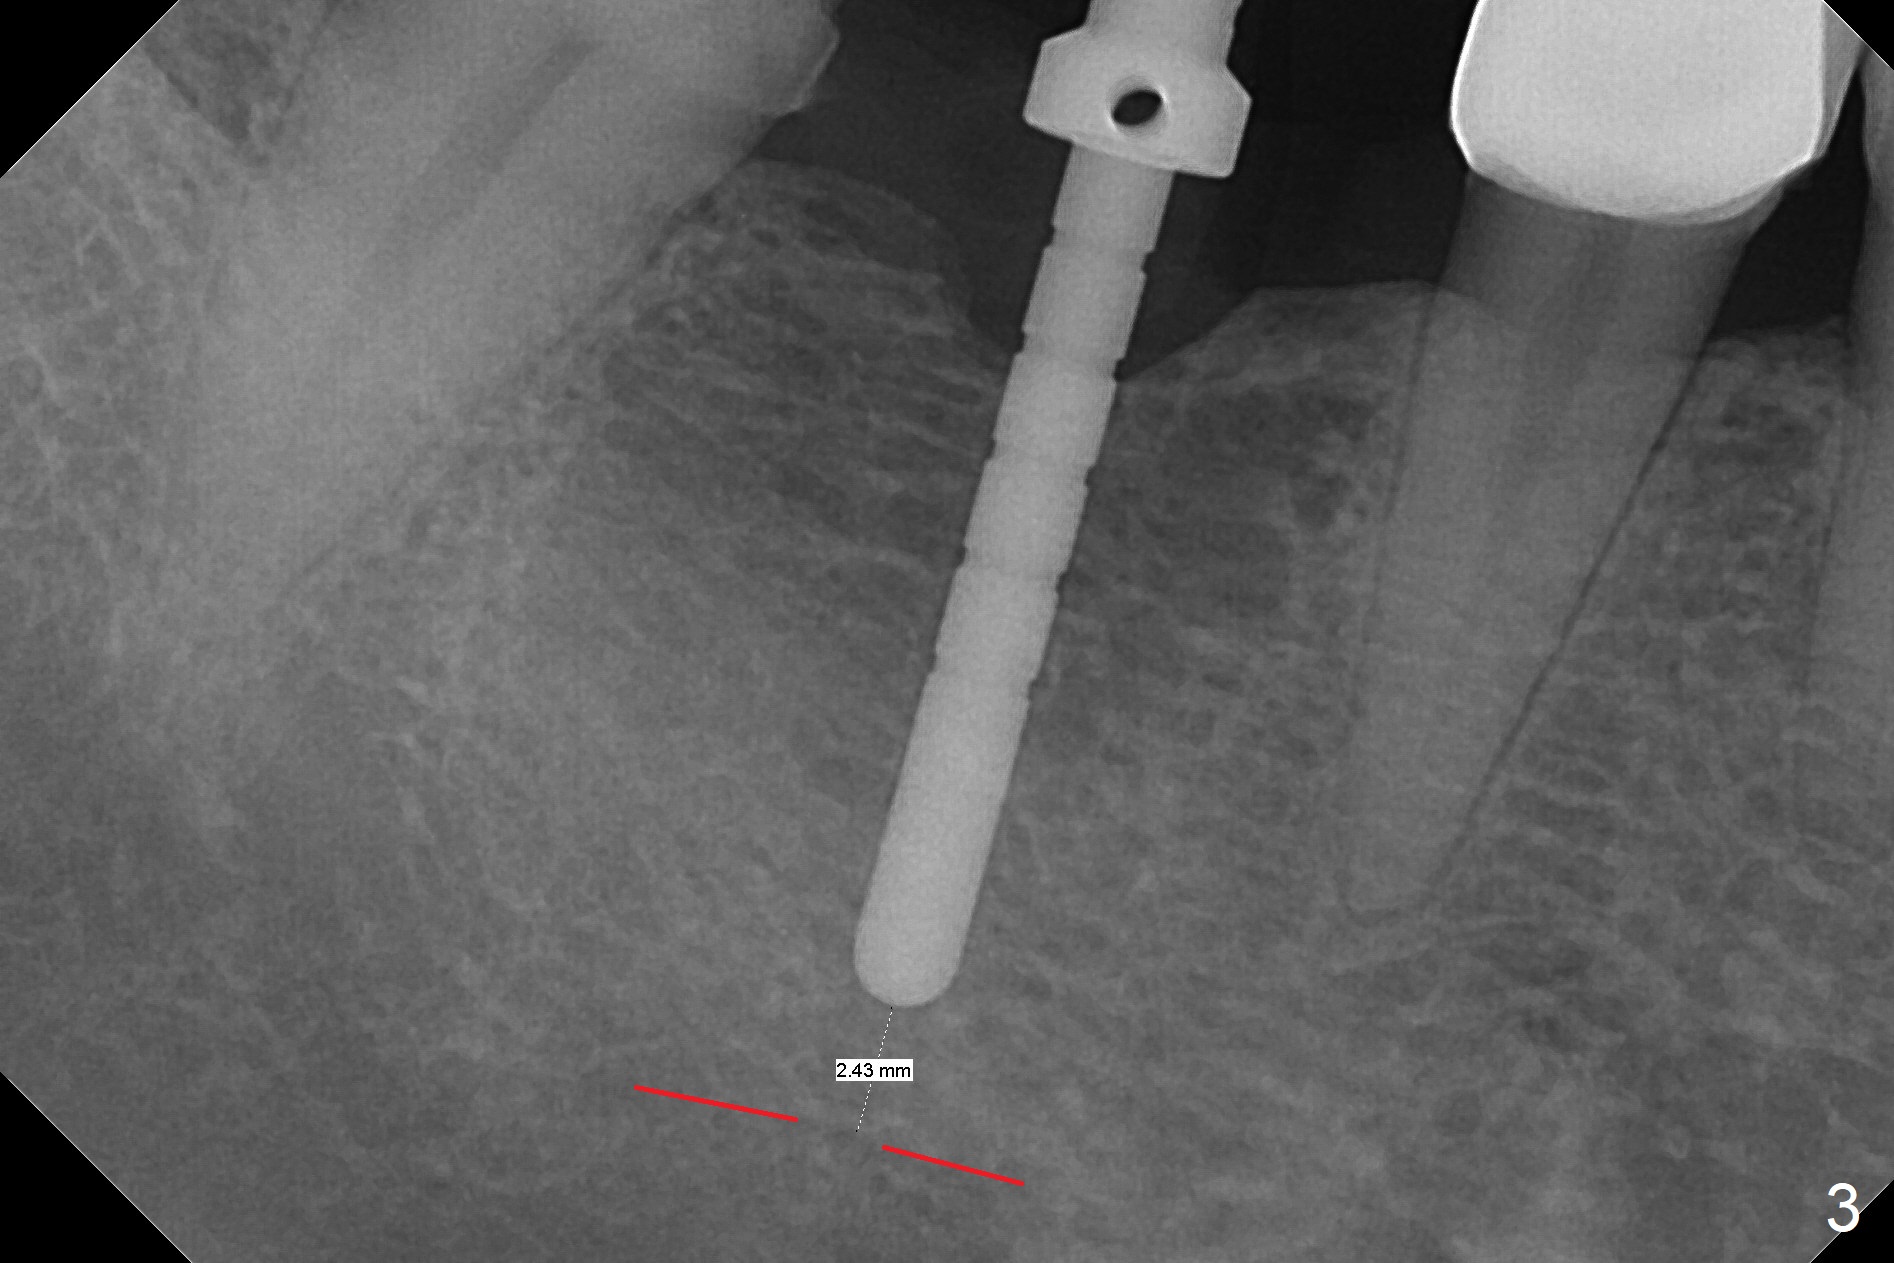

The apparently narrow ridge at #30 before bridge sectioning (Fig.1) is confirmed with incision (Fig.2). Following ridge reduction, osteotomy is initiated with 2 mm pilot drill (Fig.3). When a 3.8x12 mm SM narrow implant is placed with 40 Ncm, there is 1-2 mm cortical bone buccolingually (Fig.4,5). The thick cortices do not seem to be easy to be bent, i.e., expanded. RCT is finished at #31 one month post implant placement (Fig.6,7), the flattened ridge appears to have started to undergo remodeling. Ridge reduction makes it possible for the implant to remain subcrestal postop (Fig.4). The bone surrounding the implant may reduce the likelihood of implant fracture. The crowns at #30 and 31will be fabricated together with light occlusion at #30. In fact the splinted provisional dislodges. There appears dense bone formation 3 months postop (Fig.8 *). The drawback of using a SM narrow implant is that a narrow abutment has to be used (4.8x4(4.5) mm). The implant crown is dislodged immediately after the patient finishes lunch. Following recementation, the occlusion is reduced. In fact, UF or IBS has no such drawback: the implant could be small, but the abutment could be large. One year post cementation, the crown at #31 needs recementation (Fig.9); the bone density next to the coronal implant increases (*).